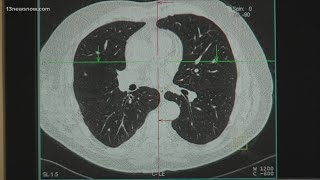

Study shows increase in cancer types affecting women, younger people video

Study shows increase in cancer types affecting women, younger people

Study shows increase in cancer types affecting women, younger people Study shows cancer cases on the rise among young women

Canadian Study Reveals Significant Increase in Breast Cancer Diagnoses for Women in Their 20s & 30s Cancer in women and young people is increasing, study finds

Cancer in women and young people is increasing, study finds New study finds rising cancer rates in young women

New study finds rising cancer rates in young women Study: Certain cancers becoming more common in younger people

Study: Certain cancers becoming more common in younger people More women, younger adults being diagnosed with cancer, study finds

More women, younger adults being diagnosed with cancer, study finds